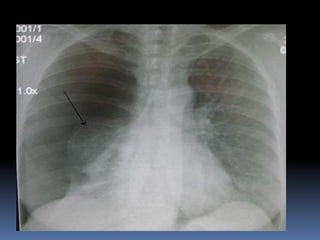

Abnormal Findings

Un equality of chest movement

Dullness on percussion

Decrease air entry

Tachypenic

heamothorax

chest tube